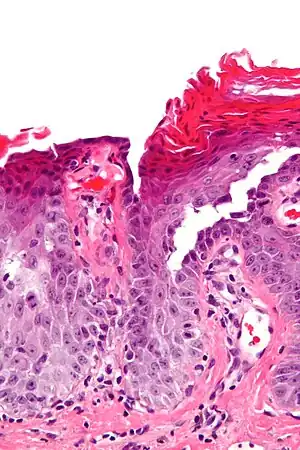

| Micrograph of transient acantholytic dermatosis, showing subcorneal separation and acantholysis. H&E stain. | |

It is characterized histologically by acantholysis,[3] with or without dyskeratosis.[4] Once confirmed, most cases of Grover's disease last six to twelve months, which is why it was originally called "transient". However it may last much longer. Nevertheless, it is not to be confused with relapsing linear acantholytic dermatosis.